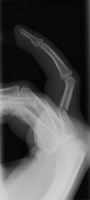

- Click on the image for a larger versionALateral radiograph of the hand. This demonstrates an angulated fracture of the fourth proximal phalanx.